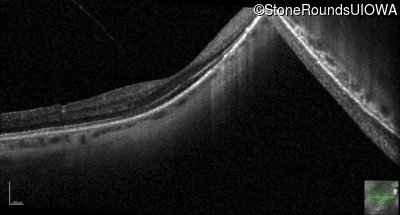

Optical Coherence Tomography - Right - 20/40 +2

Exemplar / OCT Stack